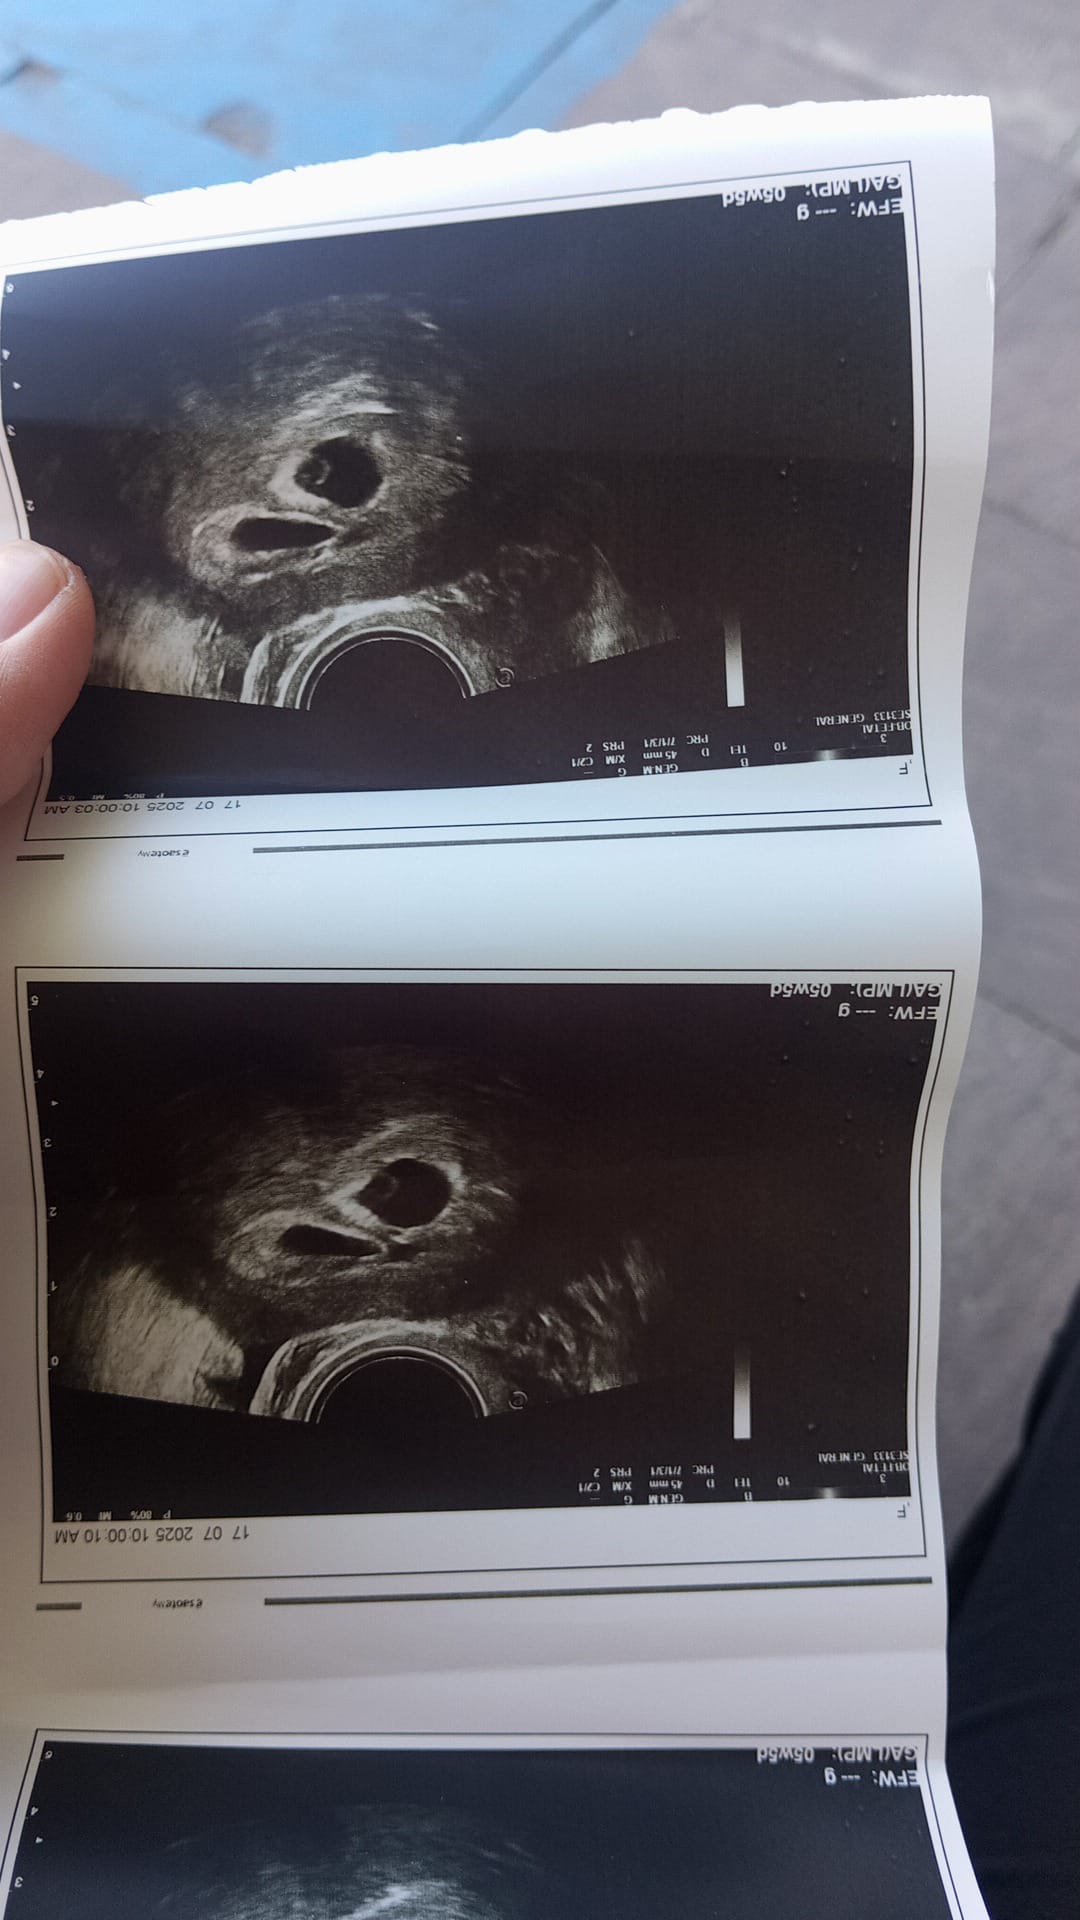

Erkek gibi kuzum

Evet canım bildin Erkek ![]()

Erkek bebiş kesesi gibi

Canım devletler yanlış cinsiyet söylüyorlar bazen bunun için özele gitsem kesin bı bilgi alabilirmiyim sence yarın 2 tarama yapılacak 3 ve 4 cu taramaya gerek olurmu acaba

Kuzum ben özele gittiğim halde başka bir özelde 13+3 de öğrendim cinsiyetini bebeğimin bence makinenin kalitesine bağlı bı de Dr tabi işinin ehli olmalı